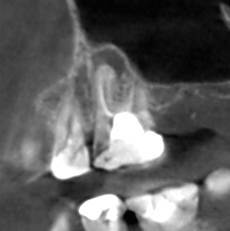

Александр В.В. Опубликовано 16 декабря, 2023 Автор Поделиться Опубликовано 16 декабря, 2023 Здравствуйте! Провёл лечение этого зуба, а гранулёма и боли остались. Прошу совета. Рассказываю по порядку. 1. До перелечивания этого зуба (шестнадцатый) были постоянные воспаления десны из-за разрушенной коронки зуба и неровных краёв пломбы в поддесневой части со стороны отсутствующего соседнего зуба. Также были боли при прикосновении пальцем десны в проекции корней зуба со стороны щеки, то есть, примерно там, где находится гранулёма. При этом припухлости этой области я не замечал. 2. На первом этапе лечения были рассверлены каналы, в том числе и ранее не найденный, и на 7 дней заложен препарат для растворения остатков пломбировочного материала. Также была установлена временная пломба. Уже после первого посещения я заметил, что ушла боль при прикосновении пальцем проекции корней. Но 2-3 дня периодически происходило выделение бурой жидкости из носа в виде капель при наклоне головы. Зуб не болел, ничего не опухало. 3. На втором этапе были удалены остатки пломбировочного материала из корней, заложен препарат кальция для «лечения» и снова установлена временная пломба. Точно не знаю, для чего применяется кальций. То ли как антисептическое средство, то ли для восстановления костной ткани. Опять несколько дней наблюдалось выделение жидкости из носа. Болей не было три недели ни в области проекции корней, ни десны со стороны отсутствующего зуба, а потом опять начала болеть десна скорее всего из-за разрушения временной пломбы. С кальцием ходил 30 дней. 4. На третьем этапе были запломбированы все каналы, установлен стекловолоконный штифт и восстановлена коронка зуба с помощью пломбировочного материала, но при этом зуб был выведен из прикуса. Стоматолог предупредил, что зуб может болеть 2 недели, как это бывает после пломбирования. На этот раз никаких выделений из носа не было. Болей или опухания тоже не было. Но примерно через 8 дней опять начала болеть десна, как со стороны отсутствующего зуба, так и в проекции корней, причём, мне кажется, что даже сильнее, чем раньше. Возможно, это связано с тем, что я начал пытаться жевать этим зубом и более смело пользоваться зубной щёткой. Новые снимки зуба показали, что гранулёма осталась на своём месте. Вопросы. 1. Нормально ли то, что гранулёма осталась, несмотря на проведённое лечение? 2. На снимке потемнение десны справа от зуба – это воспаление? В чём может быть его причина? 3. Что появилось в пазухах? На снимках, сделанных год назад, этого не было. 4. Почему проходили боли на первых этапах лечения и появились снова после его окончания? 5. Что делать дальше? Ждать, что само пройдёт или принимать какие-то меры? Систематически таблетки не пил. Только однократный приём НПВС после каждого посещения стоматолога. Сейчас провожу полоскание зуба различными препаратами и мажу разными мазями и гелями для дёсен. Ссылка на комментарий